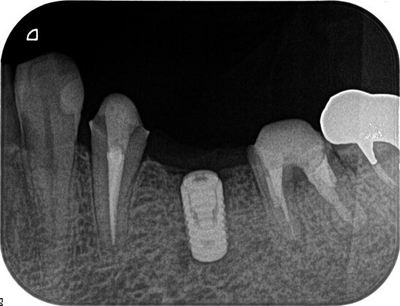

レントゲンで確認します。